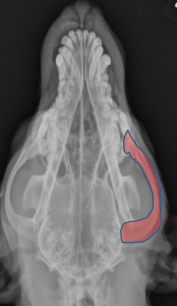

ID.

Mandible

ID Radiographic View

Lateral